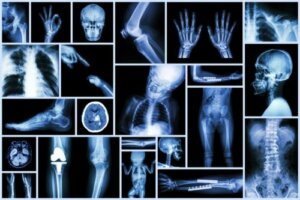

Net als elk ander beeldvormend onderzoek kunnen we met röntgenstralen aspecten van het lichaam van kinderen leren kennen die we met het blote oog niet kunnen zien.

Op de spoedeisende hulp helpt een eenvoudige röntgenfoto ons bijvoorbeeld:

- De diagnose van een breuk te bevestigen.

- De aanwezigheid van een vreemd voorwerp in de luchtweg op te sporen.

- Of te bepalen of buikpijn chirurgische behandeling vereist.